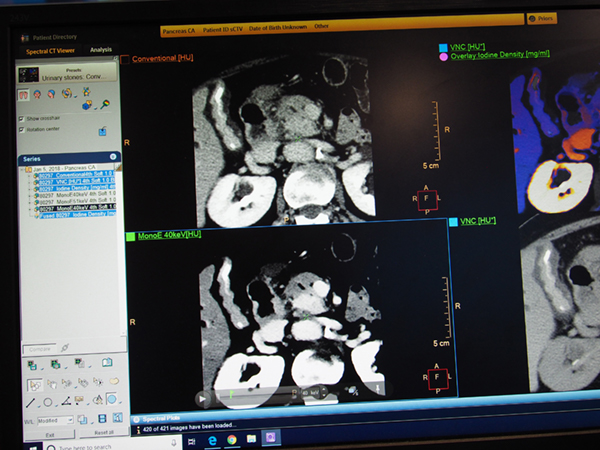

仮想単色X線画像“MonoE”の使用例として,日本国内の膵臓がん症例が紹介された。造影後期の撮影では造影剤の洗い出しが進むため,通常画像(120kVp)ではコントラストが低下するが,MonoEの40keVではコントラストが上昇し,病変の視認性が向上する様子が示された。MonoEのkeVは,ワークステーション上でスライドバーを使ってインタラクティブに調整できるため,ユーザーにとって最適なコントラストの画像を,あとから容易に作成することができる。

膵臓がん症例:通常画像(120kVp,上)とMonoE(40keV,下)

MonoEはインタラクティブに任意のkeV画像を作成可能

スペクトラルイメージングの切り替えも容易に行える。